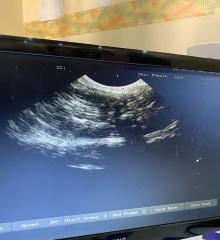

Ultrasound

Ultrasound is used for reasons, such as:

During pregnancy and fetal surgery